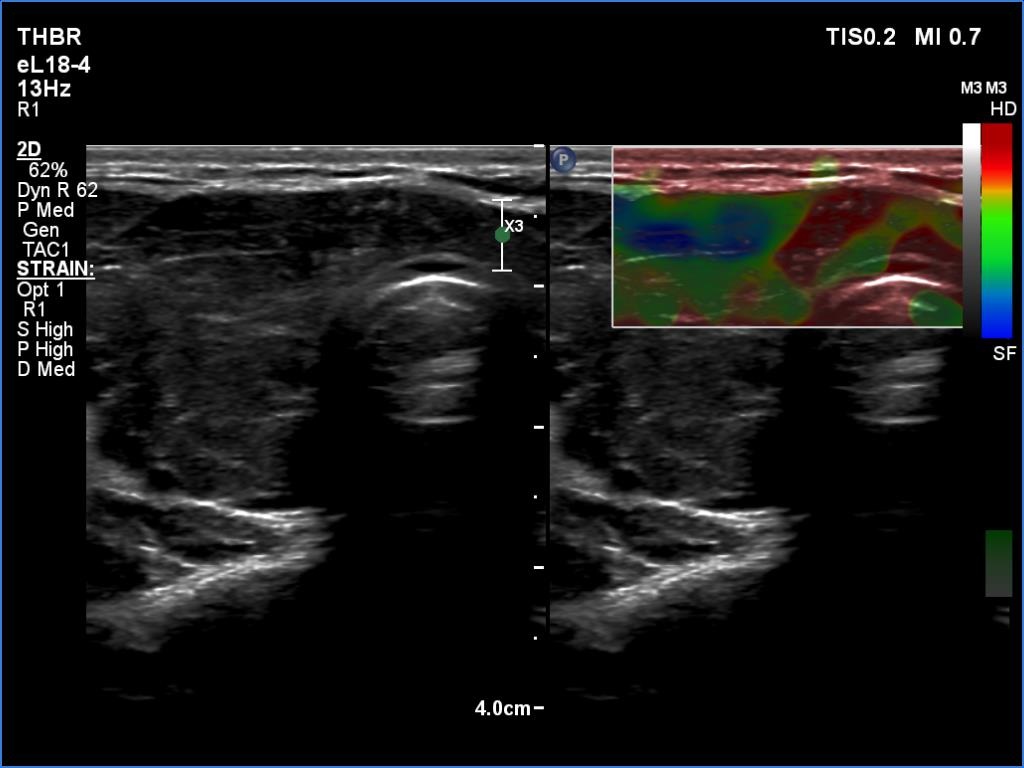

Ultrasonography. The thyroid was moderately hypoechoic and inhomogeneous. There was a deeply hypoechoic lesion in the isthmus which presented microcalcifications. Compared with the extranodular tissue, the nodule was much less vascularized on Doppler and microflow imaging but was harder on elastography.

There were two conditions which favored that the discrete lesion in the isthmus is a true nodule and not a more active focus of the underlying Hashimoto's thyroiditis. Firstly, the palpation which itself was suspicious of a cancer. Second, the presence of microcalcifications. It is worth comparing the similarly deep hypoechoic areas in the left lobe with the presentation of the cancer focus.